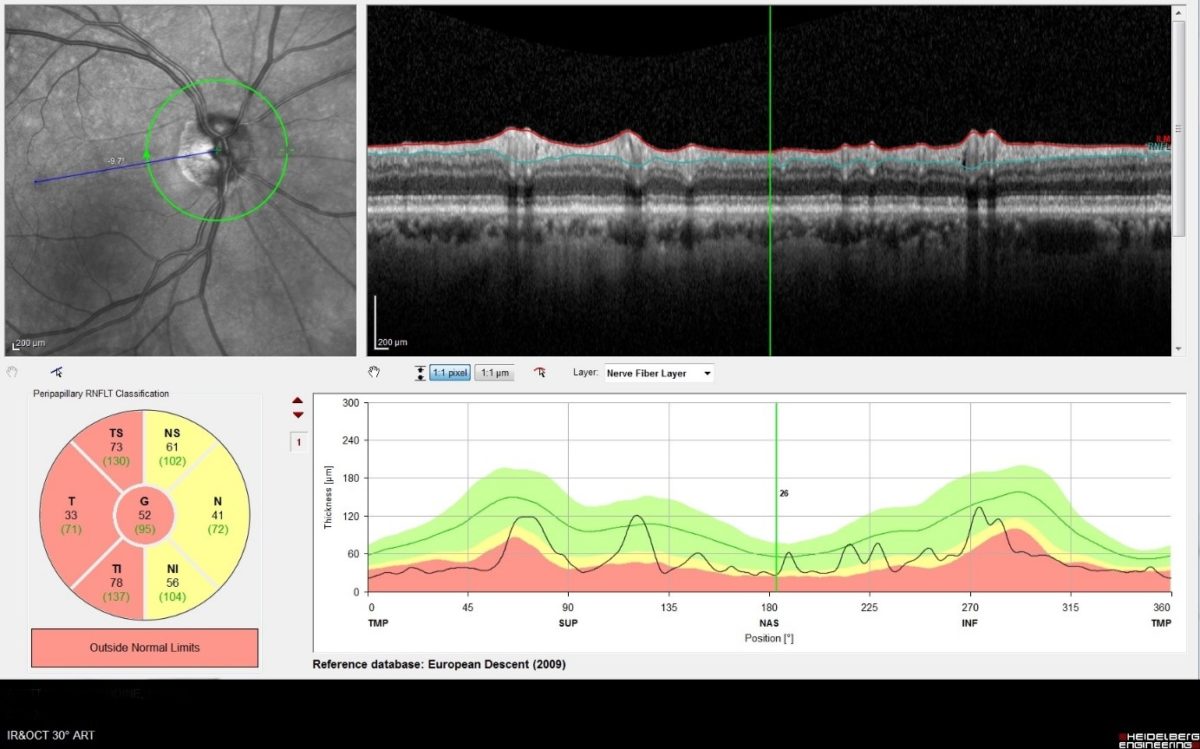

D’autres techniques automatisées ont été développées pour quantifier les mêmes déficits. La plus fréquemment utilisée est la tomographie à cohérence optique (OCT). Elle fournit des plans de coupe autour de l’axe de la papille pour évaluer l’épaisseur et le volume du disque et de la couche des fibres optiques.